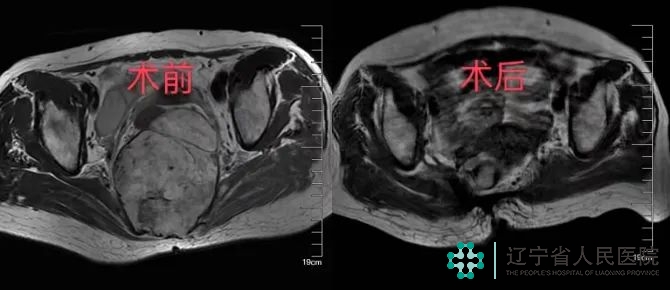

术前、术后MRI对比

整个手术持续大约4小时,非常顺利,术中有效地控制了出血量,在肿瘤完整切除的同时又保护了患者的大小便功能,术后病理结果确诊肿瘤为脊索瘤。